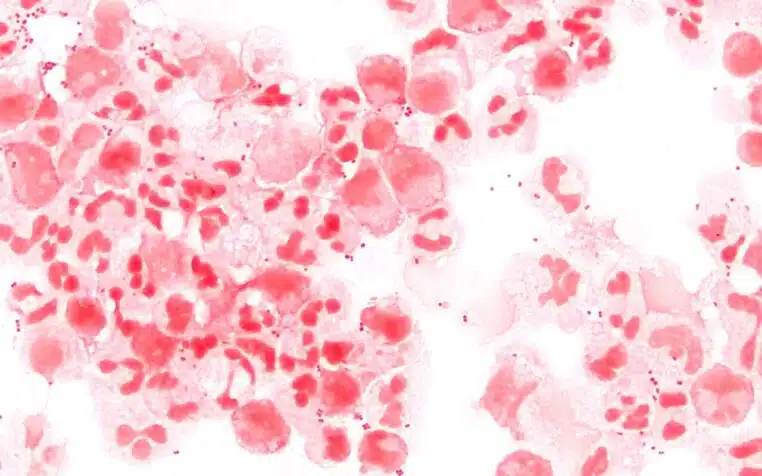

C’est précisément ce qui rend les débuts si trompeurs. Les premiers signes ressemblent souvent à ceux d’une infection banale : fièvre, fatigue, courbatures, malaise général. Ensuite, d’autres symptômes peuvent apparaître, comme des vomissements, une grande sensibilité à la lumière, une raideur de nuque, des troubles de la conscience ou des taches rouges et violacées sur la peau. Pour les médecins, ce dernier signe, le purpura, constitue un signal d’alarme majeur.

Après l’urgence, la reconstruction